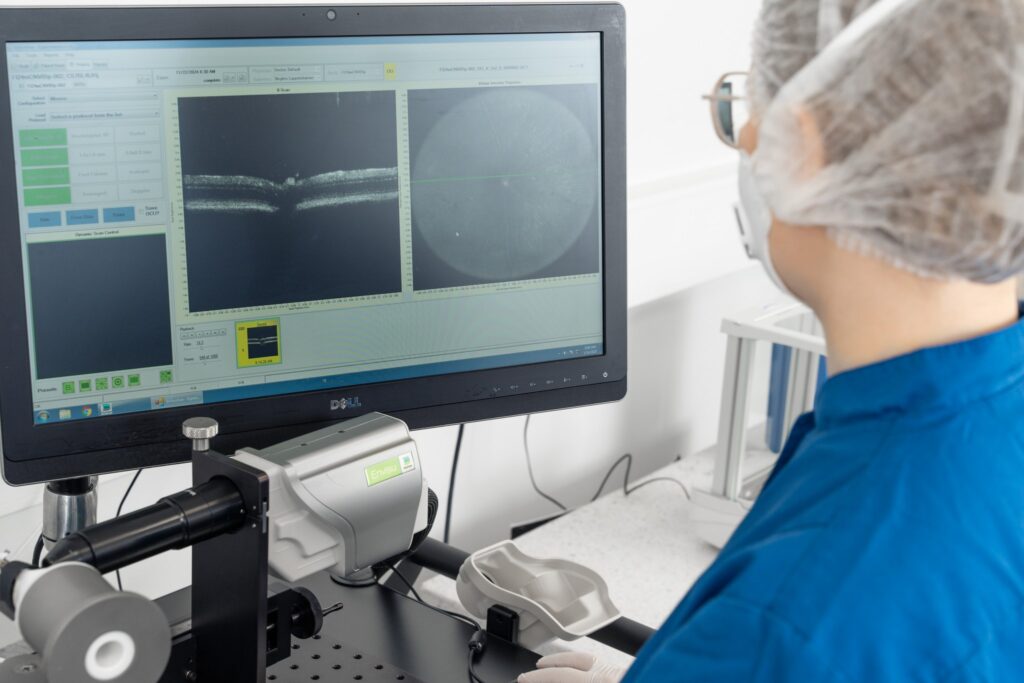

At Experimentica, we have fully implemented and validated both mouse and rat ONC models (Kalesnykas et al., 2012; Leinonen et al., 2016; Maciulaitiene et al., 2017). Our capabilities include non-invasive in vivo imaging techniques such as spectral-domain optical coherence tomography (SD-OCT) to monitor structural changes in the retina. We also offer functional assessments, including pattern electroretinography (pERG), visual evoked potential (VEP), and optomotor reflex (OMR), to evaluate visual function. Additionally, we provide immunostaining and unbiased quantification of RGCs, as well as optic nerve damage evaluation.

– SD-OCT imaging to quantitatively assess individual retinal layer thickness